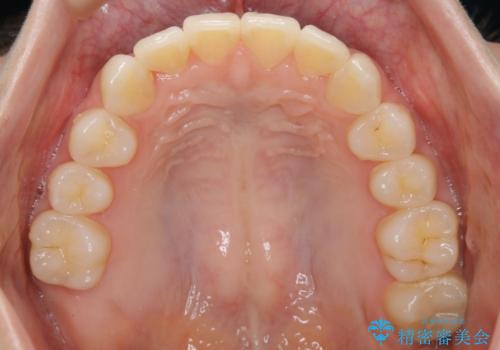

- 笑った時の歯の見え方を治したいとのことで矯正相談にいらっしゃいました。

一見そこまで大きなガタつきはないようにも見えますが、前歯の角度の不揃いや噛み合わせのズレなどから見え方に影響が出てしまっていました。

抜歯は全く必要のないレベルのガタつきだったため、マイクロインプラントを用いて歯全体を後方に移動させていくことできれいな歯並びを獲得することができました。

マウスピースとマイクロインプラントを組み合わせることで、抜歯をしなくても歯並びを治すためのスペースを作ることができます。奥歯から順に移動させていくので前歯に変化が出るまでには時間がかかりますが、どの分健康な歯を抜歯することなく理想的な歯並びを手に入れることができます。